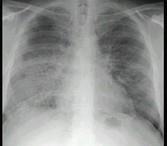

问题 24岁女性,咳嗽、进行性胸闷、气促2月,支气管镜如图,镜下可见大量米汁样分泌物。影像学检查如图。可能的诊断是 ( )

选项 A.肺泡蛋白沉积症 B.支气管扩张 C.肺炎 D.肺结核 E.先天性肺囊肿

答案 A